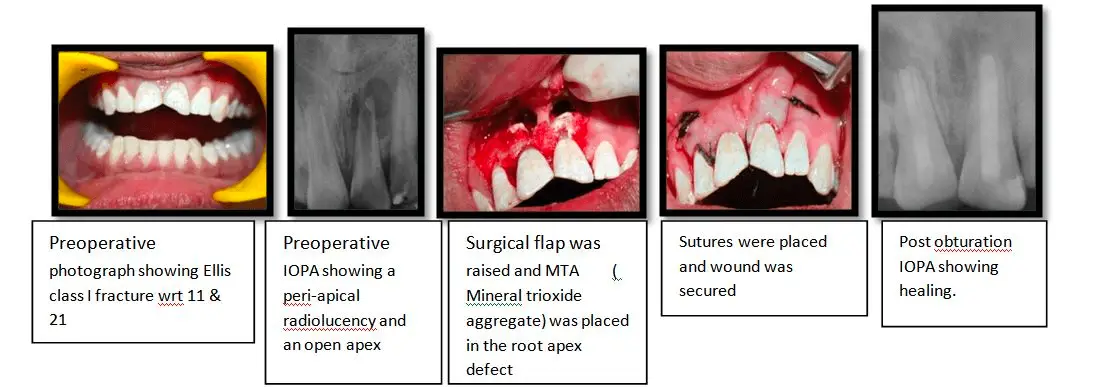

Apicoectomy

In this case, the patient presented with pain in the upper front teeth since 10 days and gave a history of trauma 6 yrs back. No history of swelling and medication was given, on intra-oral examination, Ellis class 1 fracture w.r.t 11 & 21 was revealed. Radiographic examination showed a Peri apical radiolucency and an open apex w.r.t 11 & 21.the diagnosis was established as symptomatic peri-apical radiolucency w.r.t 11,21 a treatment plan of peri-apical surgery w.r.t 11 & 21 was charted and carried out.